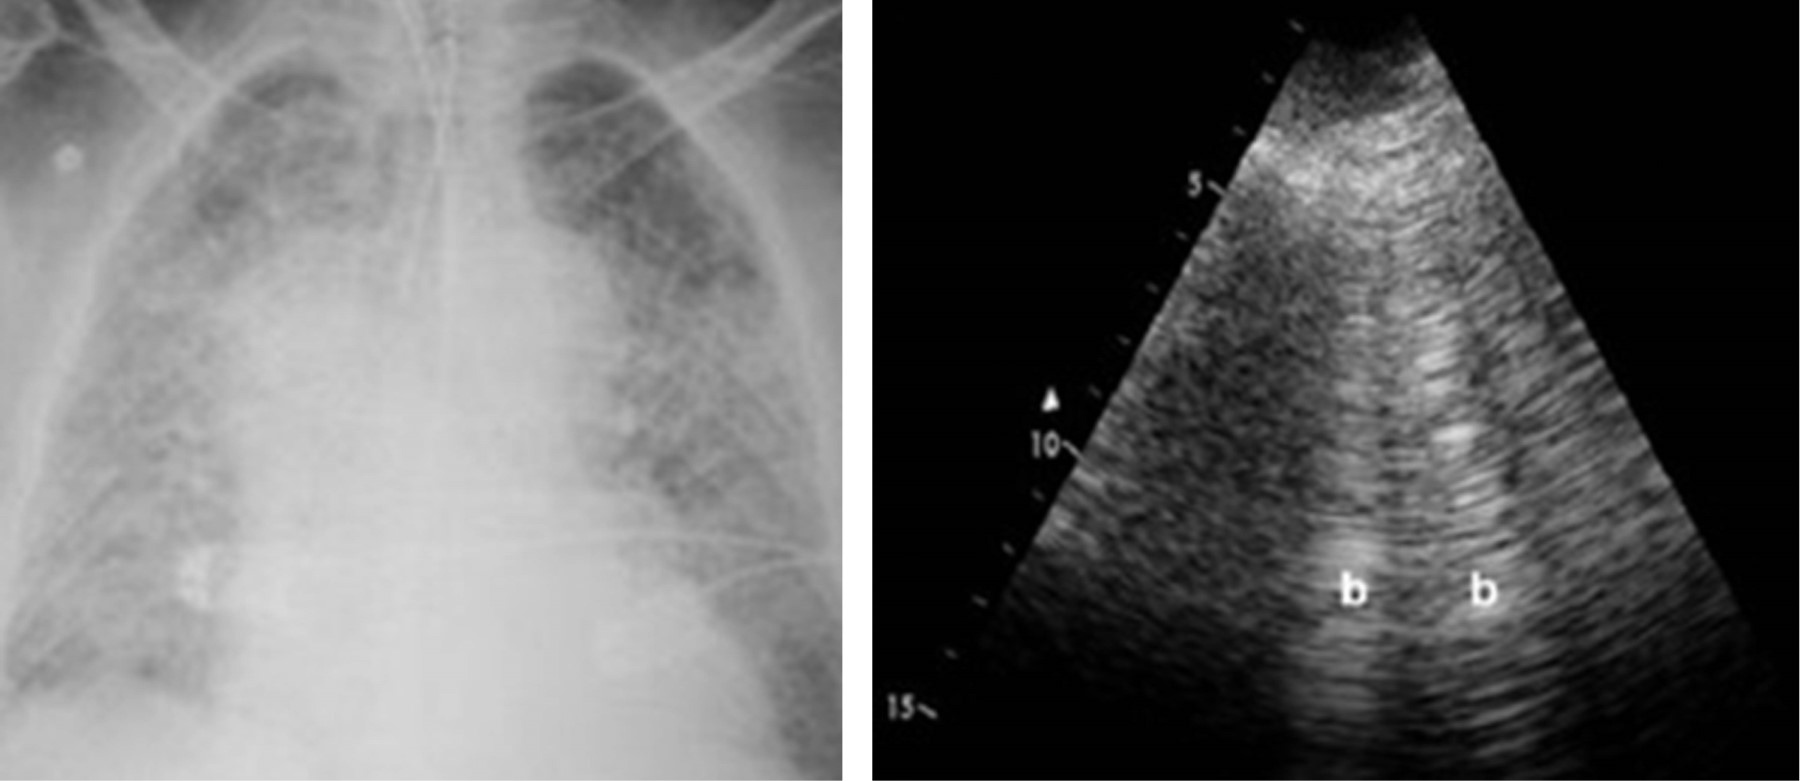

Hemorragia alveolar difusa asociada a E-VALI: revisión de la literatura y reporte de un caso en México

López-Fermín, Jorge1,2; Pérez-Nieto, Orlando Rubén1,2; Deloya-Tomas, Ernesto1,2; Carrión-Moya, Jorge1; Castillo-Gutiérrez, Gabriela1; Olvera-Ramos, María Guadalupe1; de la Torre-Rittscher, Andrea Guadalupe1; Mondragón-Labelle, Tania Olga1; Pozos-Cortés, Karen Pamela1; Trejo-Osornio, David Alejandro1; Zamarrón-López, , Eder Iván2,3; Secchi-del Río, Roberto1